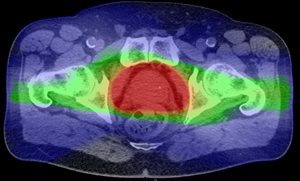

Proton Therapy

Conventional X-Ray Therapy

Red: High Radiation Dose

Green: Intermediate Radiation Dose

Blue: Low Radiation Dose